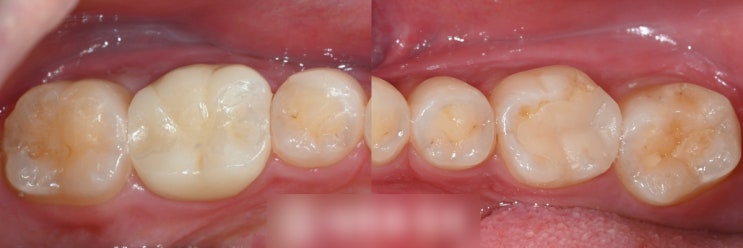

신촌치과 골드 인레이 하방에 진행된 치아 충치, 레진, 이맥스 인레이, MTA tomy 지르코니아 크라운

안녕하십니까! 대표원장 조민기입니다. 치아 충치는 겉면은 선이나 점으로 보여도 안쪽으로 충치가 깊게 퍼...